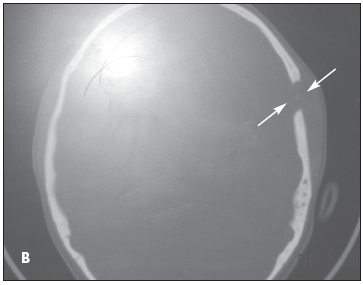

X-ray films of the skull showed a circular defect and an overlying soft tissue swelling (A). CT scans of the head confirmed the solitary bone defect in the skull without any involvement of the brain (B). The complete blood cell count was within normal limits.